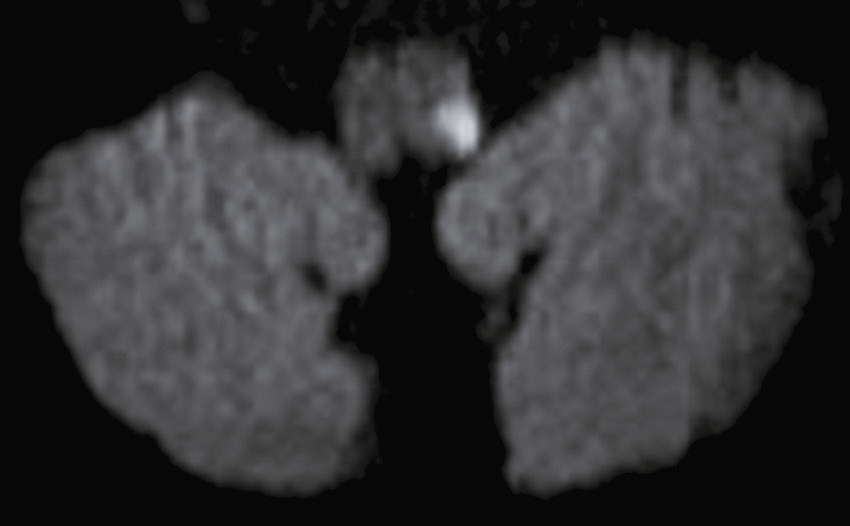

Vous débutez un traitement par benzodiazépine, vitaminothérapie B1, B6, PP, réhydratation par sérum salé et immunoglobulines polyvalentes intraveineuses associées à une héparine de bas poids moléculaire à dose isocoagulante. Le lendemain matin, le patient s’est aggravé d’un point de vue clinique. Il n’a plus d’hallucination visuelle mais il présente maintenant une tétraparésie évaluée à 3/5 avec ataxie des quatre membres, une dysarthrie, des troubles de la déglutition, et une ophtalmoplégie bilatérale. Un bilan biologique a été prélevé avant votre arrivée : numération formule sanguine : Hb : 13,8 g/dL, leucocytes : 8 600/ mm3, plaquettes : 332 000/mm3, ionogramme sanguin : Na+ : 142 mmol/L, K+ : 4,2 mmol/L, clairance de la créatininémie : 92 mL/min, glycémie : 5,8 mmol/L, transaminases, phosphatases alcalines, bilirubines et γ-GT normales, CRP : 3 mg/L.

Une IRM cérébrale a été également réalisée (fig. 31.4). Quelle est la séquence présentée ?

L'image montre une IRM (Imagerie par Résonance Magnétique) du cerveau humain en coupe axiale, c'est-à-dire une vue transversale du cerveau prise horizontalement. Cette image est particulièrement intéressante car elle permet de visualiser les structures internes du cerveau avec une grande précision. On peut observer les globes oculaires en haut de l'image, qui apparaissent comme deux cercles blancs. Les différentes zones du cerveau sont visibles, avec des variations de teintes qui indiquent les différentes densités des tissus cérébraux. La région centrale lumineuse correspond au tronc cérébral, une structure cruciale pour de nombreuses fonctions vitales. Les zones plus sombres autour du tronc cérébral représentent les hémisphères cérébraux. Cette image est utilisée pour diagnostiquer et évaluer diverses conditions neurologiques, telles que les tumeurs, les accidents vasculaires cérébraux, les infections, et les anomalies structurelles. L'IRM est une technique non invasive qui utilise des champs magnétiques et des ondes radio pour produire des images détaillées des organes et des tissus internes.

- A T1

- B écho de gradient

- C T2

- D T2/FLAIR

- E diffusion